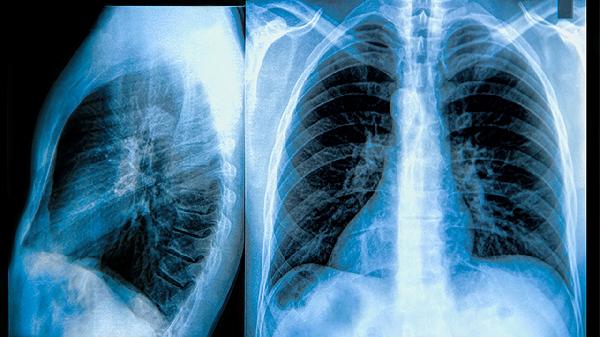

肺部斑点状密度增高影在影像学上表现为局部组织密度高于周围正常肺组织,形态不规则且边界模糊。常见于肺部感染性病变如细菌性肺炎或肺结核活动期,病灶周围常伴随渗出性改变。职业暴露史患者可能出现尘肺结节,影像特征为双肺弥漫性分布的小斑点影。部分早期肺癌也可呈现为磨玻璃样密度增高,需通过动态随访观察形态变化。肺血管异常如肺栓塞后梗死灶亦可形成三角形密度增高区。

对于长期吸烟者出现的孤立性结节,需警惕恶性可能,增强CT检查有助于评估血流灌注特征。过敏性肺炎患者可见游走性斑片影,多与接触过敏原相关。某些结缔组织病如类风湿关节炎可引发肺间质改变,表现为网状结节影伴胸膜增厚。肺水肿患者的心源性密度增高多呈蝶翼状分布,结合BNP检测可辅助诊断。慢性支气管炎急性发作时可能出现支气管壁增厚伴周围炎性渗出影。